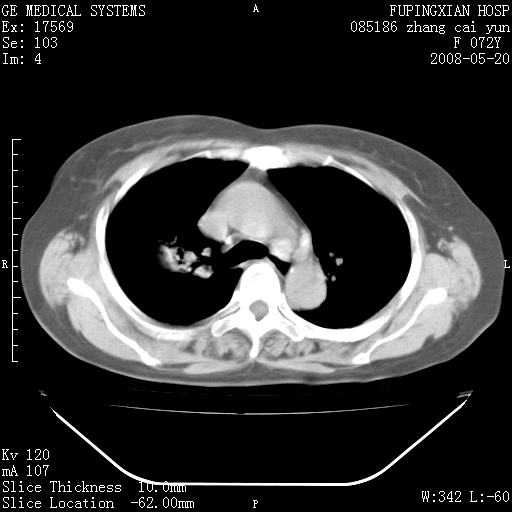

标题: CT13542:发热,咳嗽数日,经抗菌素治疗好转,请大家看排除 [打印本页]

标题: CT13542:发热,咳嗽数日,经抗菌素治疗好转,请大家看排除

右上叶支气管走行自然,未见明显管壁增厚等征像,另左主支气管起始部可见异常腔道向左侧延展左肺动脉干后方,与左下叶支气管相通,为左下叶支气管变异?

有节段性阻塞性肺炎与不张,近段支气管狭窄,周围散在肿大淋巴结影,以周围型肺癌可能性大,建议纤支镜检查。

建议纤支镜检查,考虑支气管内膜结核可能性大

右肺上叶实变影,内见支气管充气征,右上叶支气管通畅,肺门区未见软组织密度影,抗炎治疗有效,考虑炎症,建议继续抗炎治疗复查。

右肺阻塞性肺炎  不除外支气管内膜结核

考虑为:右肺上叶感染性病变。建议:1)继续抗炎治疗后复查。2)必要时行纤支镜检查。